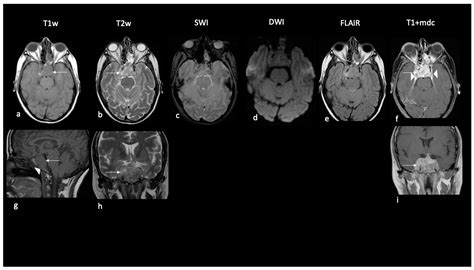

Diagnosis typically begins with advanced neuroimaging, such as MRI scans with and without contrast, to visualize the tumor's size and location. However, imaging alone is rarely sufficient. A definitive diagnosis is achieved through a surgical biopsy or total resection, followed by a rigorous pathological examination. Pathologists look for the loss of INI1 protein expression in the tumor cells, which serves as a molecular hallmark for an Atypical Teratoid Tumor.

• Atypical Teratoid Rhabdoid Tumor MRI